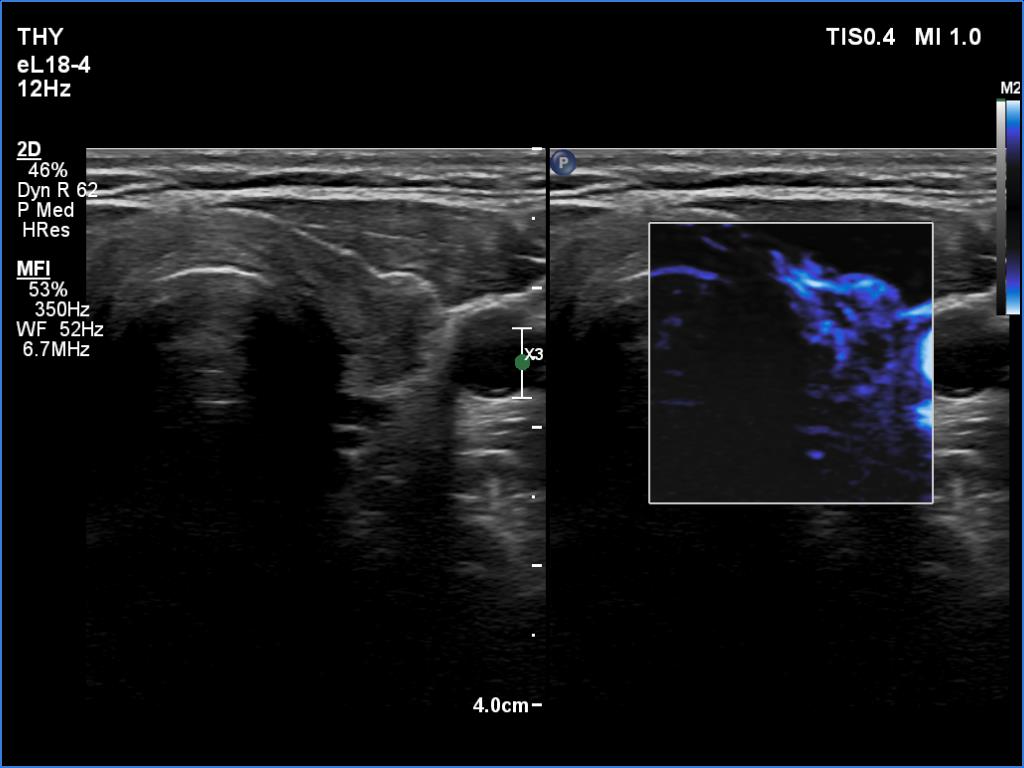

First examination (first row of images):

Ultrasonography. The thyroid was minimally hypoechoic. There was a small, discrete lesion in the upper pole of the right lobe. The left lobe had a larger and several tiny hypoechogenic lesions. The large lesion presented partly blurred, partly lobulated margins.

2. The hypoechoic lesion in the left lobe had lobulated, spiculated and not blurred margins as in the usual case of de Quervain's thyroiditis.